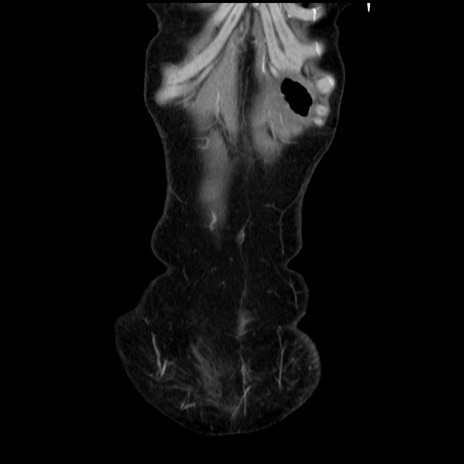

症例32(冠状断像)

【既往歴】子宮頚癌(広汎子宮全摘術、放射線療法)、腸閉塞